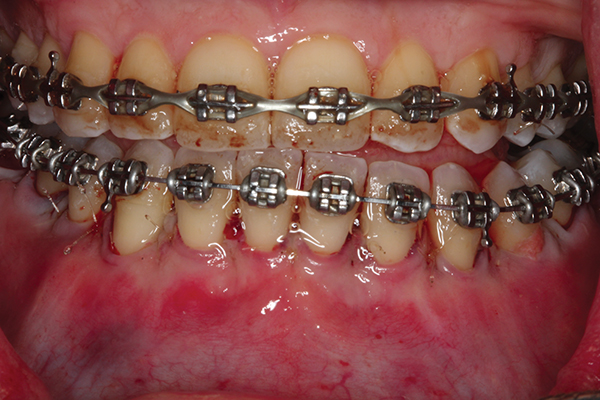

Fig 2. Full-thickness flap reflection. Note

dehiscence and fenestrations throughout. Orthodontic walls are limited to nonexistent.

Figure 2